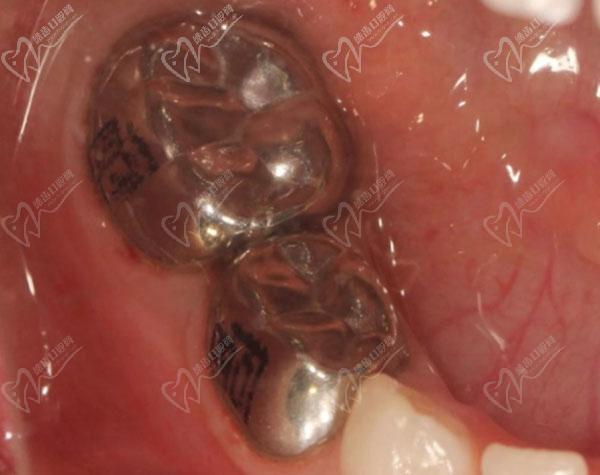

以下2种预成冠图片:

金属预成冠:

金属预成冠

金属预成冠通常会用于后牙,贴合的包裹后牙并保护牙齿,加强牙齿强度,保护恒压和乳牙能够正常替换。